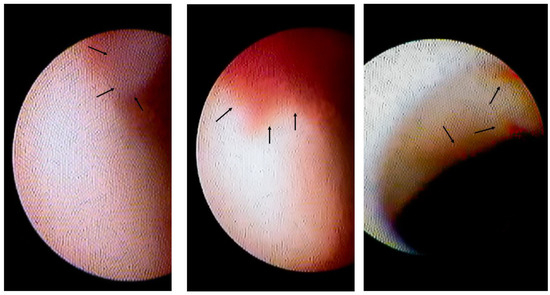

3.2. Lesion Characteristics with Intracoronary Thrombi

| Intracoronary thrombus (%) | 18 (26) | 0 (0) | <0.01 | 0 (0) | <0.01 |